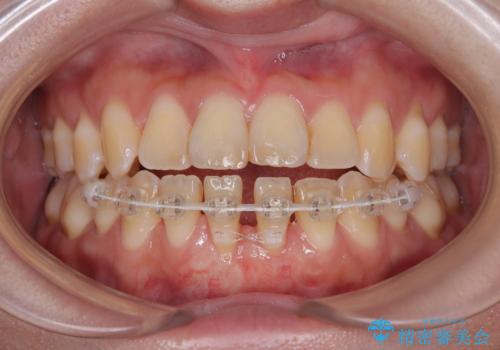

矯正の後戻りによるすきっ歯と歯肉退縮 根面被覆と部分矯正

- 学生時代の矯正治療の後戻りと、それに伴う下顎前歯西肉退縮を気にして来院された患者様です。

舌の突出癖が著しく、それが原因で後戻りと歯肉退縮を起こしている状態でした。

舌のトレーニングをしっかりと行っていくことを前提に、歯肉移植による根面被覆と、部分矯正によるすきっ歯の改善を行うこととしました。